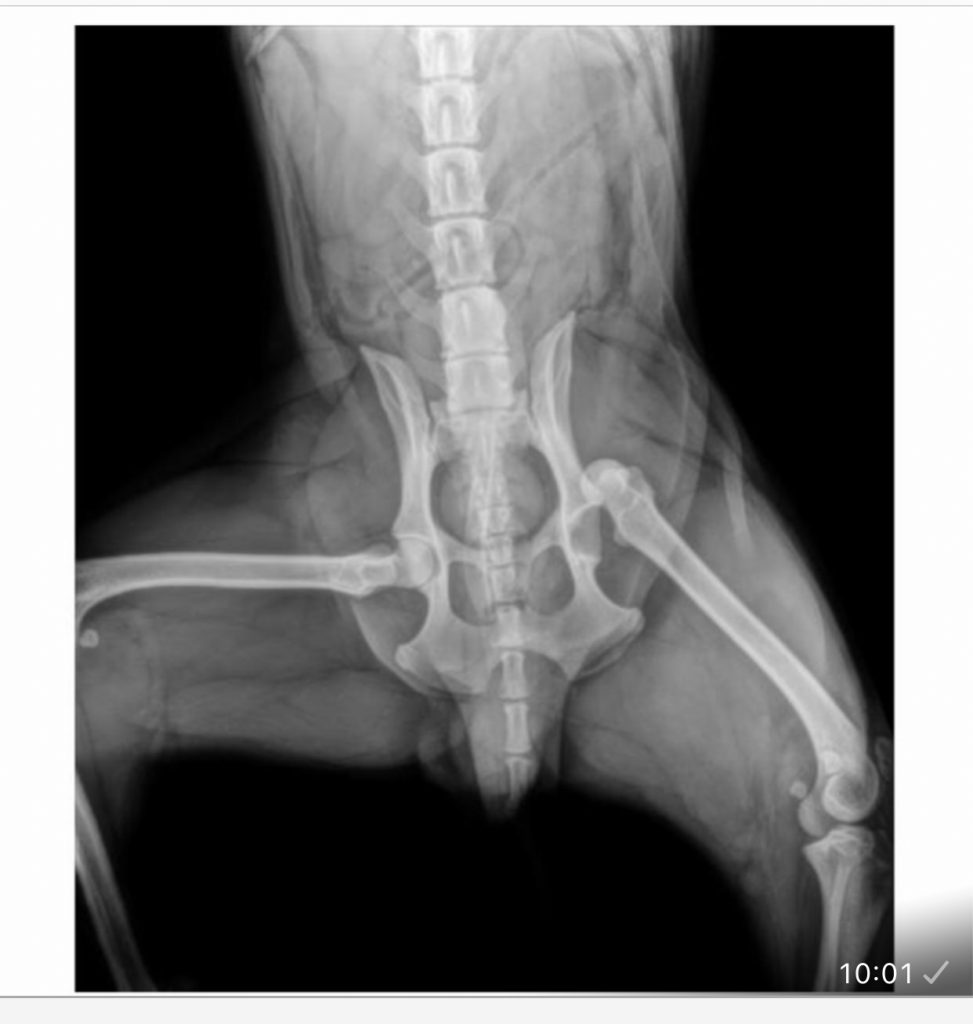

Born: 2024 – Breed: Podenco mix – Male

weighs 19 kilos.

He’s a good boy who recently came to live with us after being hit by a car, which dislocated his hip. He’s currently recovering well from surgery. Son is very easy to handle and lets us treat him; he even licks your hands while you do it. He’s a trusting dog who readily accepts your requests. He walks well on a leash and is very attentive to anything you ask of him. He gets along well with other dogs, both male and female, large and small, and we’re sure he’ll start playing with them soon. Although he’s a young Podenco, he has a very calm energy and has rested without any problems after surgery. We believe he’s a good boy who deserves a family to play and go for walks with. Despite his hip injury, he can live a normal life, going on hikes and doing anything his new family wants him to do.